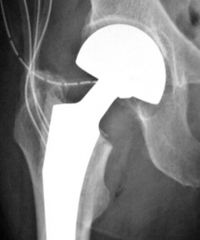

Hüftendoprothesenversorgung (HEP)

Die Therapieoption bei hochgradiger Koxarthrose ist die Wahl des endoprothetischen Gelenkersatzes. Der Ersatz durch ein künstliches Hüftgelenk erfolgt mit dem Ziel, dem Patienten Schmerzfreiheit und eine alltagstaugliche Hüftgelenkbeweglichkeit zu ermöglichen. Dabei sollte die Lebensdauer (Standzeit) der Prothese möglichst lang sein, um die Zahl notwendiger Wechseleingriffe gering zu halten.

Ein Implantatwechsel ist üblicherweise bei Implantatlockerung angebracht. Die Ursachen für eine Implantatlockerung können bei Knochensubstanzverlust im Prothesenlager, dem Ausbleiben des knöchernen Einheilens bei zementfreien Prothesen, einer akuten oder chronischen Infektion des Prothesenlagers oder einer traumatisch bedingten periprothetischen Fraktur vorliegen.

Die Standzeit der Hüft-Endoprothesen beträgt in der Regel mehr als 15 Jahre.